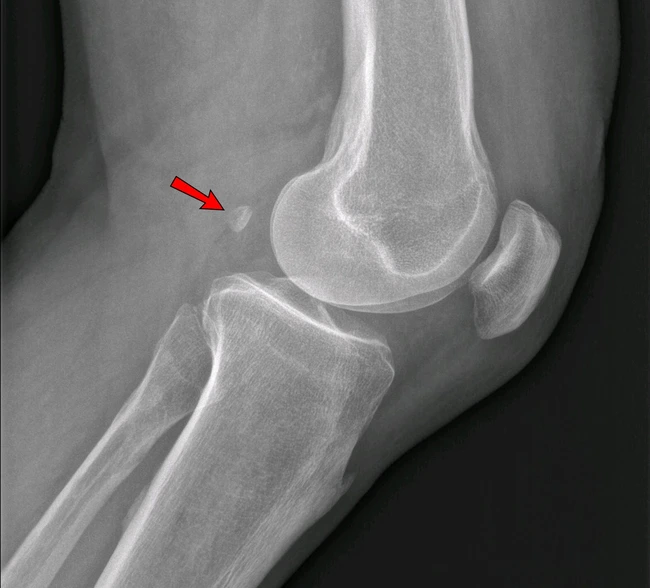

Fabella, un os în spatele genunchiului FOTO wikipedia

Propriu-zis fabella este un os de dimensiunea unei boabe de fasole, de aici și denumirea în latină, fabella însemnând „mica boabă de fasole”. Din punct de vedere științitic fabella este un os seismoid care se află în spatele rotulei genunchiului, adică chiar în spatele încheieturii genunchiului, fiind un os seismoid, acesta crește în zona tendonului unui mușchi.